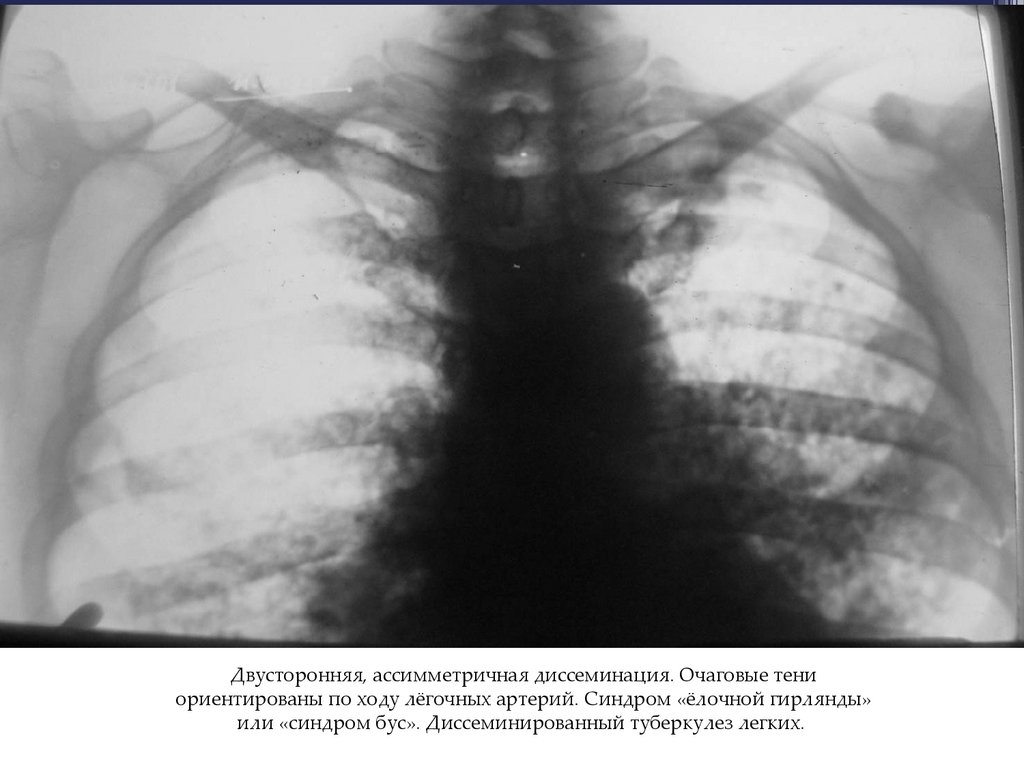

Двусторонняя, ассимметричная диссеминация. Очаговые тени

ориентированы по ходу лёгочных артерий. Синдром «ёлочной гирлянды»

или «синдром бус». Диссеминированный туберкулез легких.